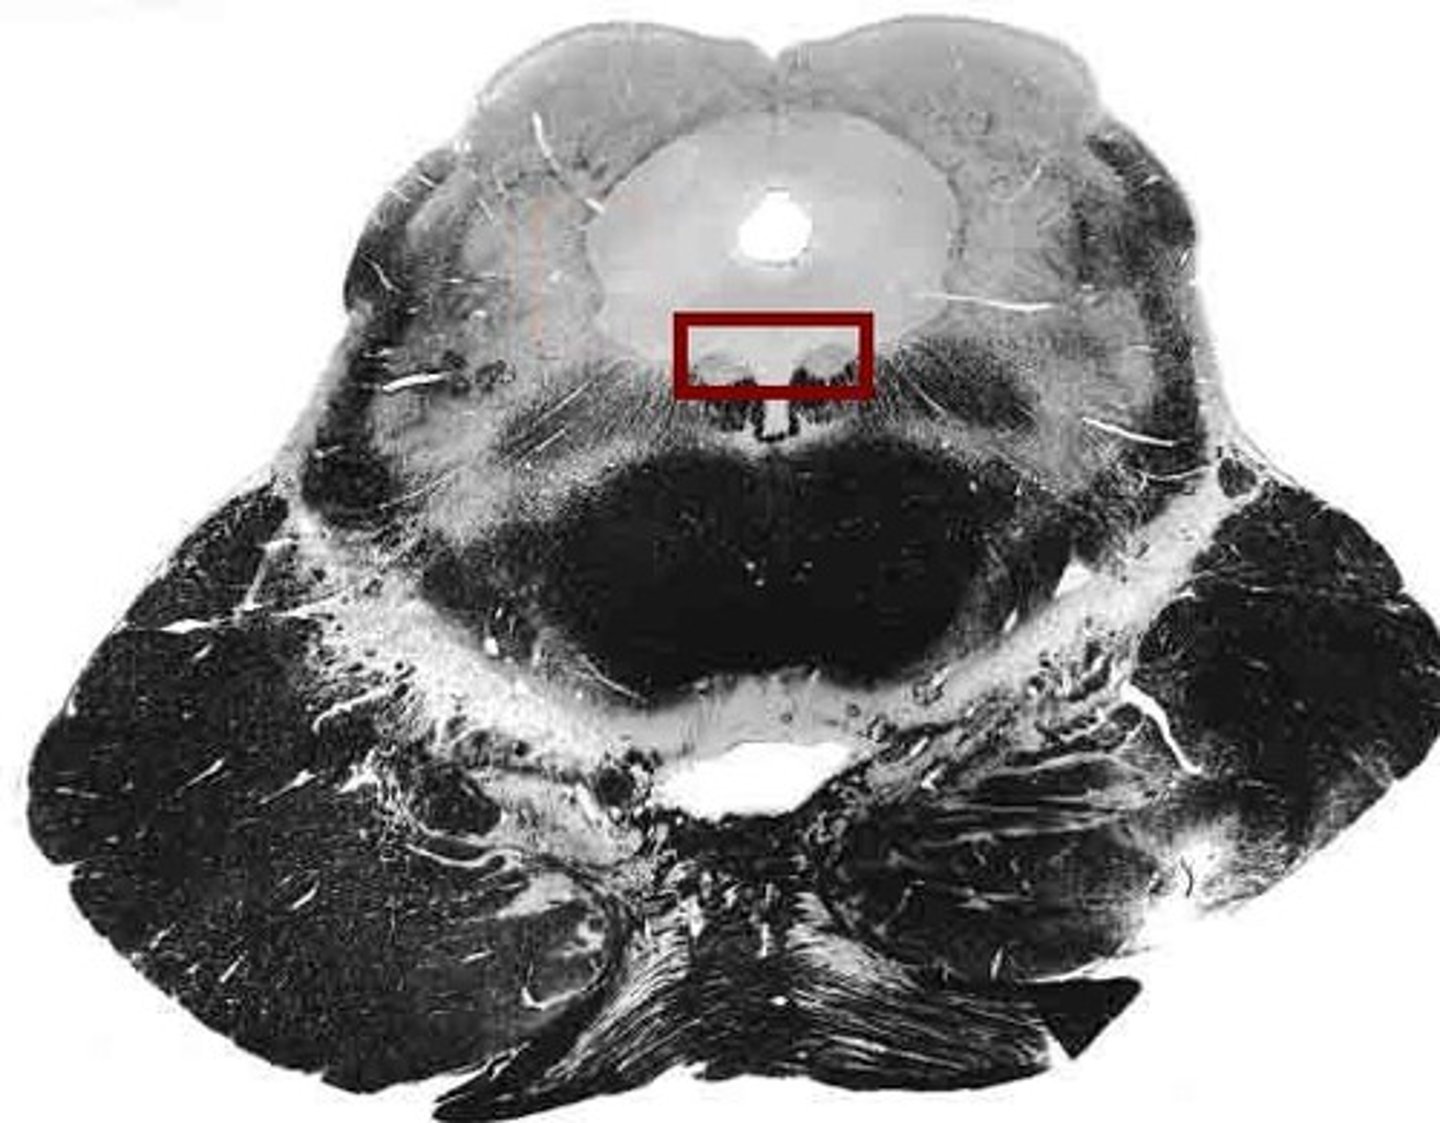

midbrain

or mesencephalon extends from pons to diencephalon. the pons is the center structure of the brain stem, located between the midbrain and the medulla oblongata

tectum of midbrain

superior and inferior colliculi

tegmentum of midbrain

involved in movement and arousal

cerebral peduncles

located on the ventral surface of midbrain. has corticospinal tract (voluntary movements) & corticobulbar tracts (motor control of face & head)